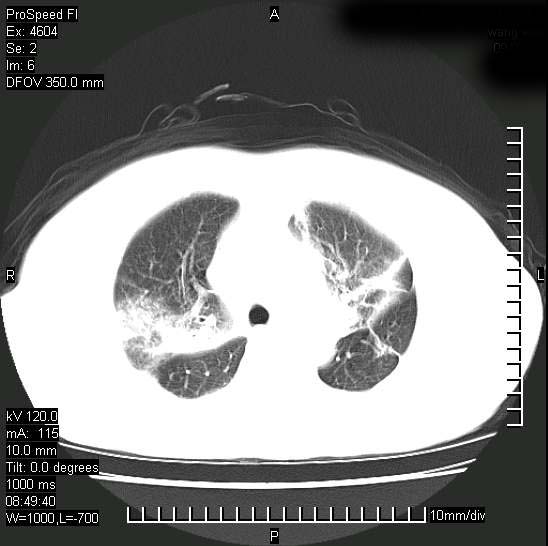

十几年前曾患肺结核,一周前突咳血约100ml,中性粒细胞稍高,诊断两上肺陈旧结核,下肺炎症,给予抗炎治疗,近几日晚上高热,39度,仍咳少量血,4天前ct及今天ct上传。

今天ct

短短几天内,病变范围明显增多扩大,以左侧明显,而且双侧出现胸水,还是考虑感染.

支持  结核ban感染,节段性肺不张,支气管内膜结核可能

短短几天内,病变范围明显增多扩大,以左侧明显,而且双侧出现胸水,我更多考虑左侧中心性肺癌并并阻塞性不张及肺炎,炎症变化也太快了!

继发性结核感染加重。左侧合并有支气管内膜结核。

无论是肿瘤还是炎症4天的时间都发展够快的,并且还在治疗中,如果说是左肺癌那么右肺的病变不好解释,本人更加倾向于炎症,左肺舌叶支气管被痰栓或血凝块堵塞,造成阻塞性肺炎。

1)两肺结核并感染。2)不排除左肺上叶中央型肺癌并阻塞性肺炎、肺不张可能;建议行纤支镜检查。3)右肺门及纵隔淋巴结肿大。4)双侧胸腔积液。

陈旧性肺结核及左下肺不张,咯血后肺部感染,双胸腔积液,高热可能与痰液引流不畅有关。